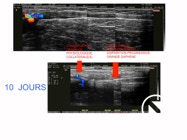

After 10 days, the process is already visible  ( see echography below ) . After 3 months, there is still a fibrous cord that will disappear within 1 year.

10 DAYS LATER AFTER LEV